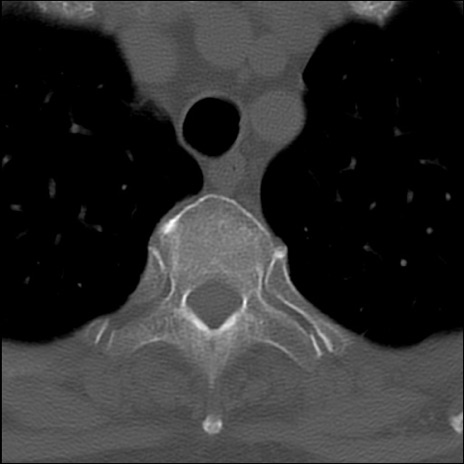

症例48 頚椎CT(横断像)

頚椎CT